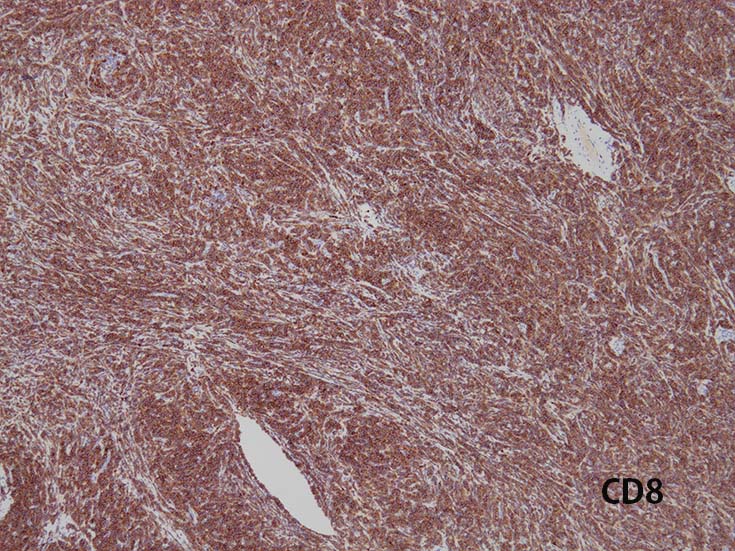

- CD1a, CD2, surface CD3 (dim), CD4, CD5, CD8は種々の程度に発現する.

- T-ALL はしばしば, CD4とCD8の double positive となる. またCD10が陽性になる

- CD4,CD8 double positiveはT-prolymphocytic leukaemiaでも認められる. CD10もPTCL(第一にはAITL)に陽性となることに注意.

- cytoplasmic CD3 のみがT-cell lineage特異的なマーカである.